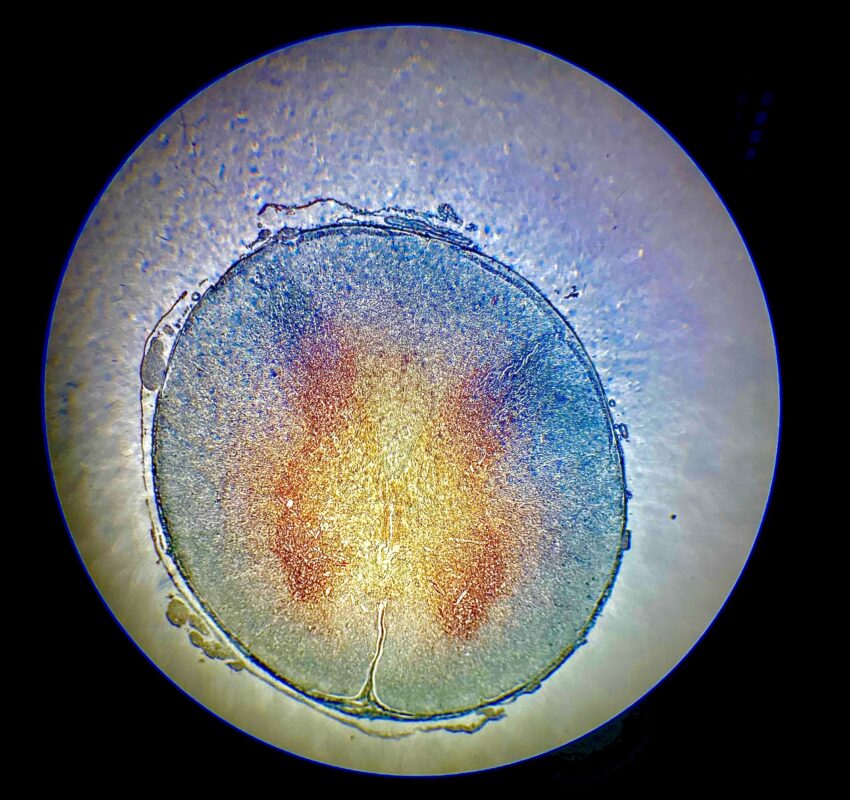

Description: Imagen de un corte transversal de médula espinal observada mediante microscopio óptico a 4x. En el centro se localiza el canal ependimario, rodeado por la sustancia gris con forma de mariposa, que se organiza en astas dorsales (posteriores) y astas ventrales (anteriores). La sustancia blanca se encuentra en la región periférica, y se diferencia de la gris por su coloración más clara. Esta imagen permite identificar con claridad la disposición general de las estructuras internas de la médula espinal y resulta útil para el estudio básico del sistema nervioso central.